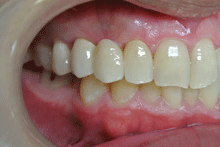

オールセラミックス

金属を使わずに全てセラミックを使用し、光の透過性を上げる事により自然な白い歯に回復させる方法です。

現在では土台から白い材質(ファイバーポストなど)の物を使用することにより、さらに透明感が増し天然歯に近似しています。

オールセラミックは近年進化を遂げており、強度や接着性がかなり改善され、審美的にとても優れたものと成って来ております。

オールセラミックにも色んな種類がありますが、当院ではe-max(二ケイ酸リチウムガラスセラミック、)ジルコニアセラミックスを採用しています。